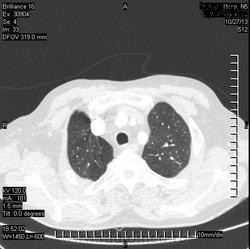

Коллега, а что, инфаркт искали? Или у Вас так окклюзии ЛА ищут? Интересно, а просто ОГК , для искл. пневмонии

( или инфаркт-пневмонии) слева?

Виноват. Не все вчера успел выложить.ТЭЛА.

ТЭЛА слева, я правильно вижу?

Да. Слева.